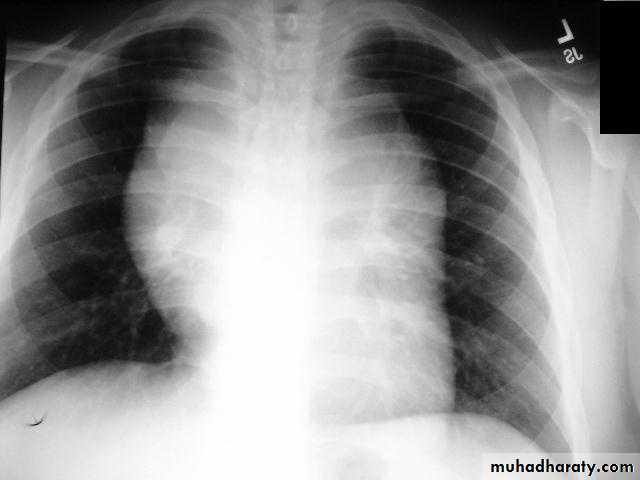

Retro sternal goiter

Radiographic featuresChest radiograph

It may show a superior mediastinal radio-opacity causing the deviation of trachea to opposite site. The superior margin of the radio-opacity/mass is untraceable (cervicothoracic sign).